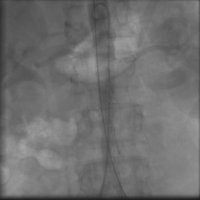

56 yaşında şeker, böbrek yetmezliği ve tansiyon hastalığı olan hastamız yol yürürken baldırlarında ağrı,ayaklarda his kaybi,sogukluk,cinsi zayıflık şikayetleriyle bize IRAK' tan başvurdu .Hastamızın bu şikayetleri 6 aydan beri giderek artmaktaymış.Yaptığımız detaylı muayeneler sayesinde hastamızın böbrek damarlarının ayrıldığı, hizanın altından aort damarının tamamen tıkalı olduğunu tesbit ettik. Aortik Tıkanma (Leriche Sendromu) teşhisi koyuğumuz hastaya yaptığımız başarılı stentleme işleminden sonra tam akım sağlanarak 3 gün sonra şikayetlerinde azalmayla taburcu edilmiştir.